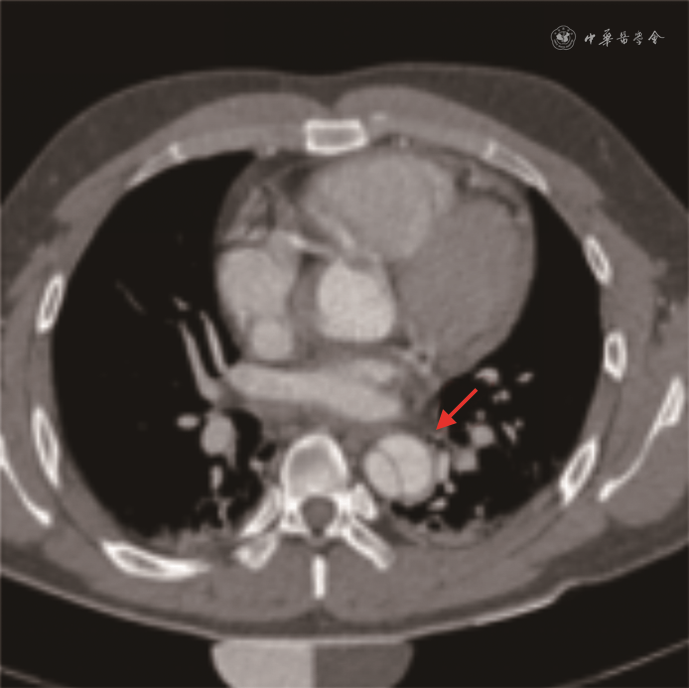

患者男,27岁,体重75 kg,身高170 cm,2018年8月因胸痛就诊于空军军医大学附属西京医院心血管外科。患者于15 h前无明显诱因感胸背部剧烈疼痛,伴心悸、气短、胸闷,无发热,无咳嗽、咳痰,无痰中带血,无腹痛、腹胀,无恶心、呕吐,无呕血、便血,能平卧,无夜间阵发性呼吸困难,无下肢水肿,无头晕、晕厥。面容正常,表情自如,神志清楚,查体合作。查体:体温36.5 ℃,脉搏78次/min,呼吸14次/min。心前区饱满,心尖搏动未见异常,位于胸骨左锁骨中线内侧1.5 cm。触诊心尖搏动位置同前,左锁骨中线内侧1.5 cm,未触及震颤,未触及心包摩擦感。心脏相对浊音界不大。听诊心率78次/min,律齐,未闻及早搏,心音可,各瓣膜区听诊未闻及病理性杂音。无异常血管征。血压126/71 mmHg(1 mmHg=0.133 kPa),否认高血压病史。吸烟15年,平均10支/d。计算机断层扫描血管造影术检查提示主动脉A型夹层(图1)。

基因组合检测及Sanger测序发现患者的COL3A1基因存在c.998G>T(p. Gly333Val)杂合突变(图2A),即COL3A1基因编码区第998位碱基由G突变为T,导致编码的Ⅲ型胶原蛋白序列发生改变,即第333位氨基酸由甘氨酸(Gly)突变为缬氨酸(Val)。Sanger测序显示此家系中患有主动脉夹层动脉瘤的弟弟也携带此变异(图2B),而体健的父亲未携带此变异(图2C),按照孟德尔遗传规律,推测变异遗传自腹膜后血管破裂去世的母亲(家系图谱见图3),这一基因型-表型关联性符合家系共分离(pathogenic supporting 1,PP1[2]);生物学软件如尺度不变特征变换(0)、多态性表型v2(1.0)、Mutation Taster(1.000)等多个软件预测该突变位点是“有害的”(pathogenic supporting 3,PP3),Mutation Taster中的保守性分析提示该位点在多个物种间是保守的(图4);同一氨基酸位点至少存在1个不同氨基酸改变的可能致病变异p.Gly333Asp(pathogenic moderate 5,PM5);根据ExAC数据库、千人数据库、gnomAD 数据库分析,该变异位点的人群频率暂无记录(pathogenic moderate 2,PM2)。根据美国医学遗传学与基因组学会遗传变异分类标准与指南,c.998G>T突变评级为可能致病(证据为PP1+PP3+PM5+PM2)。结合患者临床表现,确诊为血管型Ehers-danlos综合征(Ehers-Danlos syndrome,vascular type,vEDS)。患者入院后病情进展较快,家属放弃治疗自动出院,出院后随访,患者死亡。本研究中携带突变的先证者弟弟,在进行家系遗传咨询时已告知定期随访,密切观察病情变化,并因其已婚未孕,告知其备孕前进行产前遗传咨询。患者1岁10个月的女儿因年龄尚小未进行基因检测,已告知成年后随访检测。